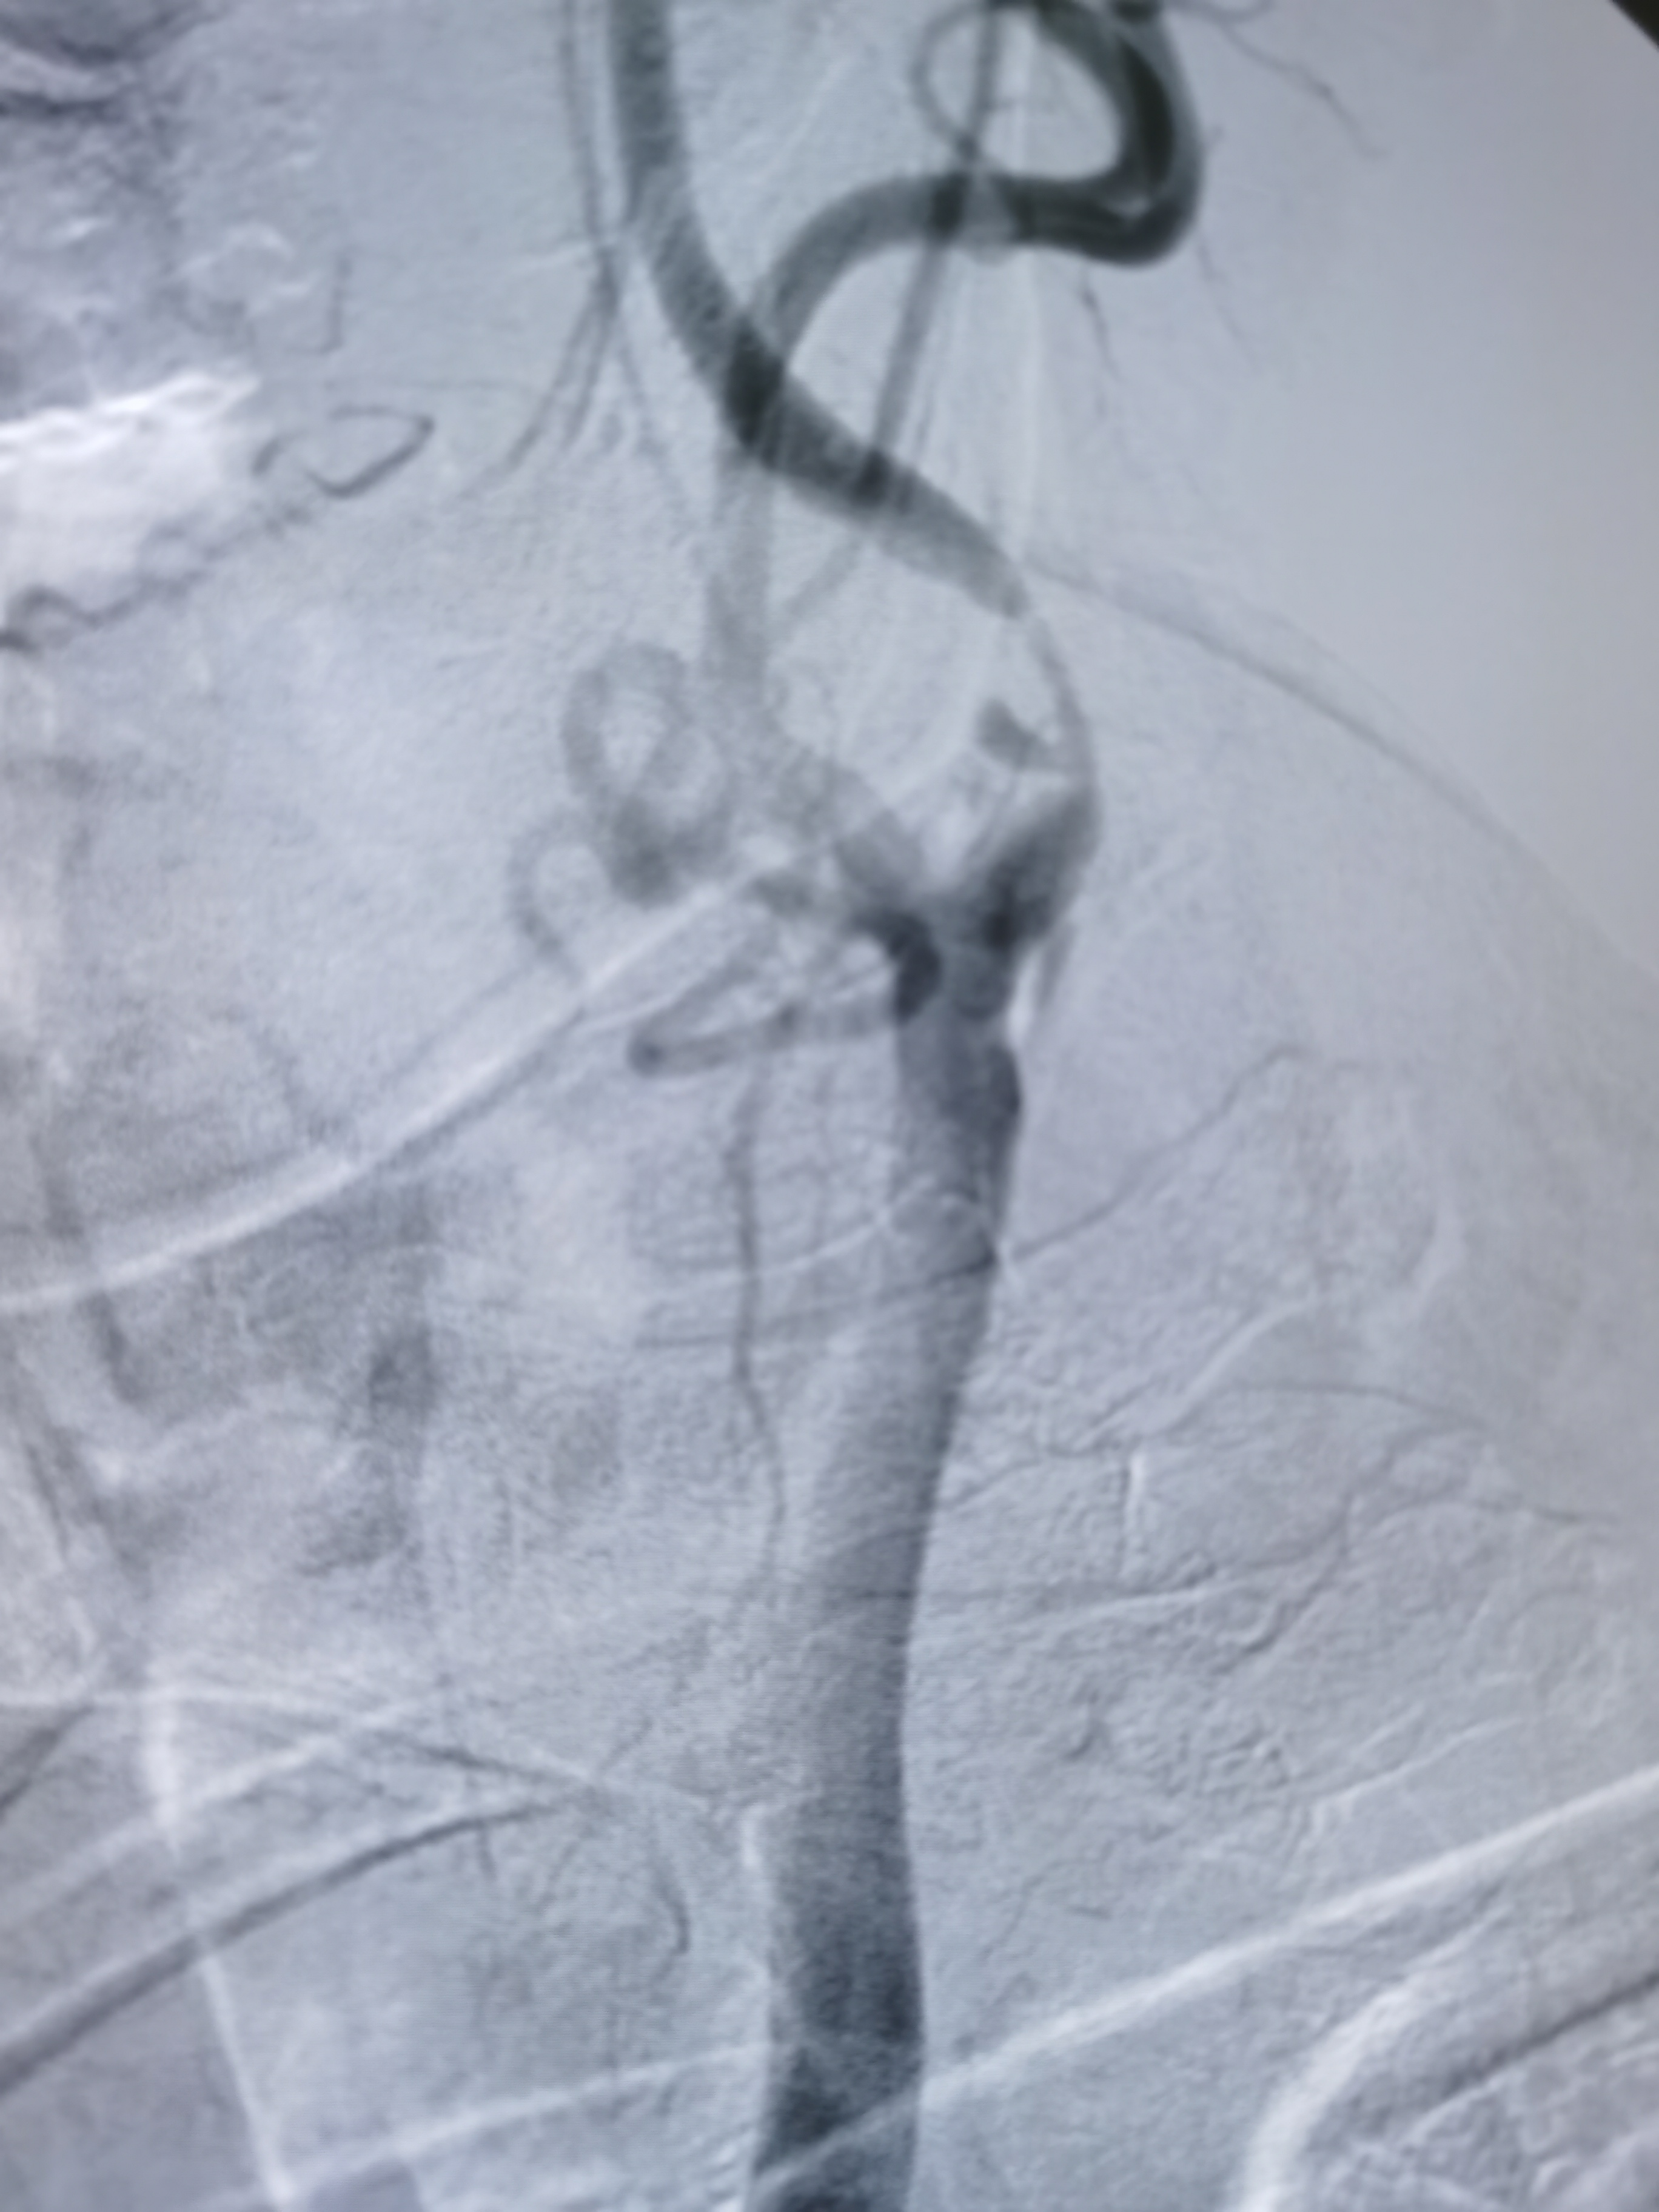

4/30球囊预扩后狭窄改善

9/40支架定位

支架释放后狭窄解除